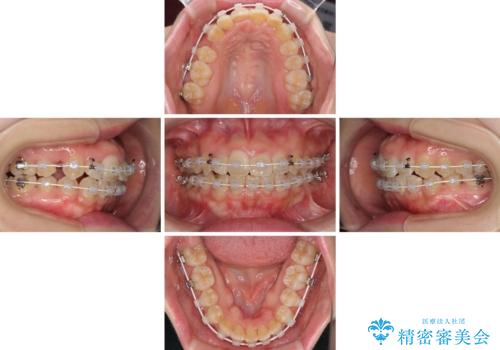

- 矯正装置

- 審美装置

- 2年

- 10-30回